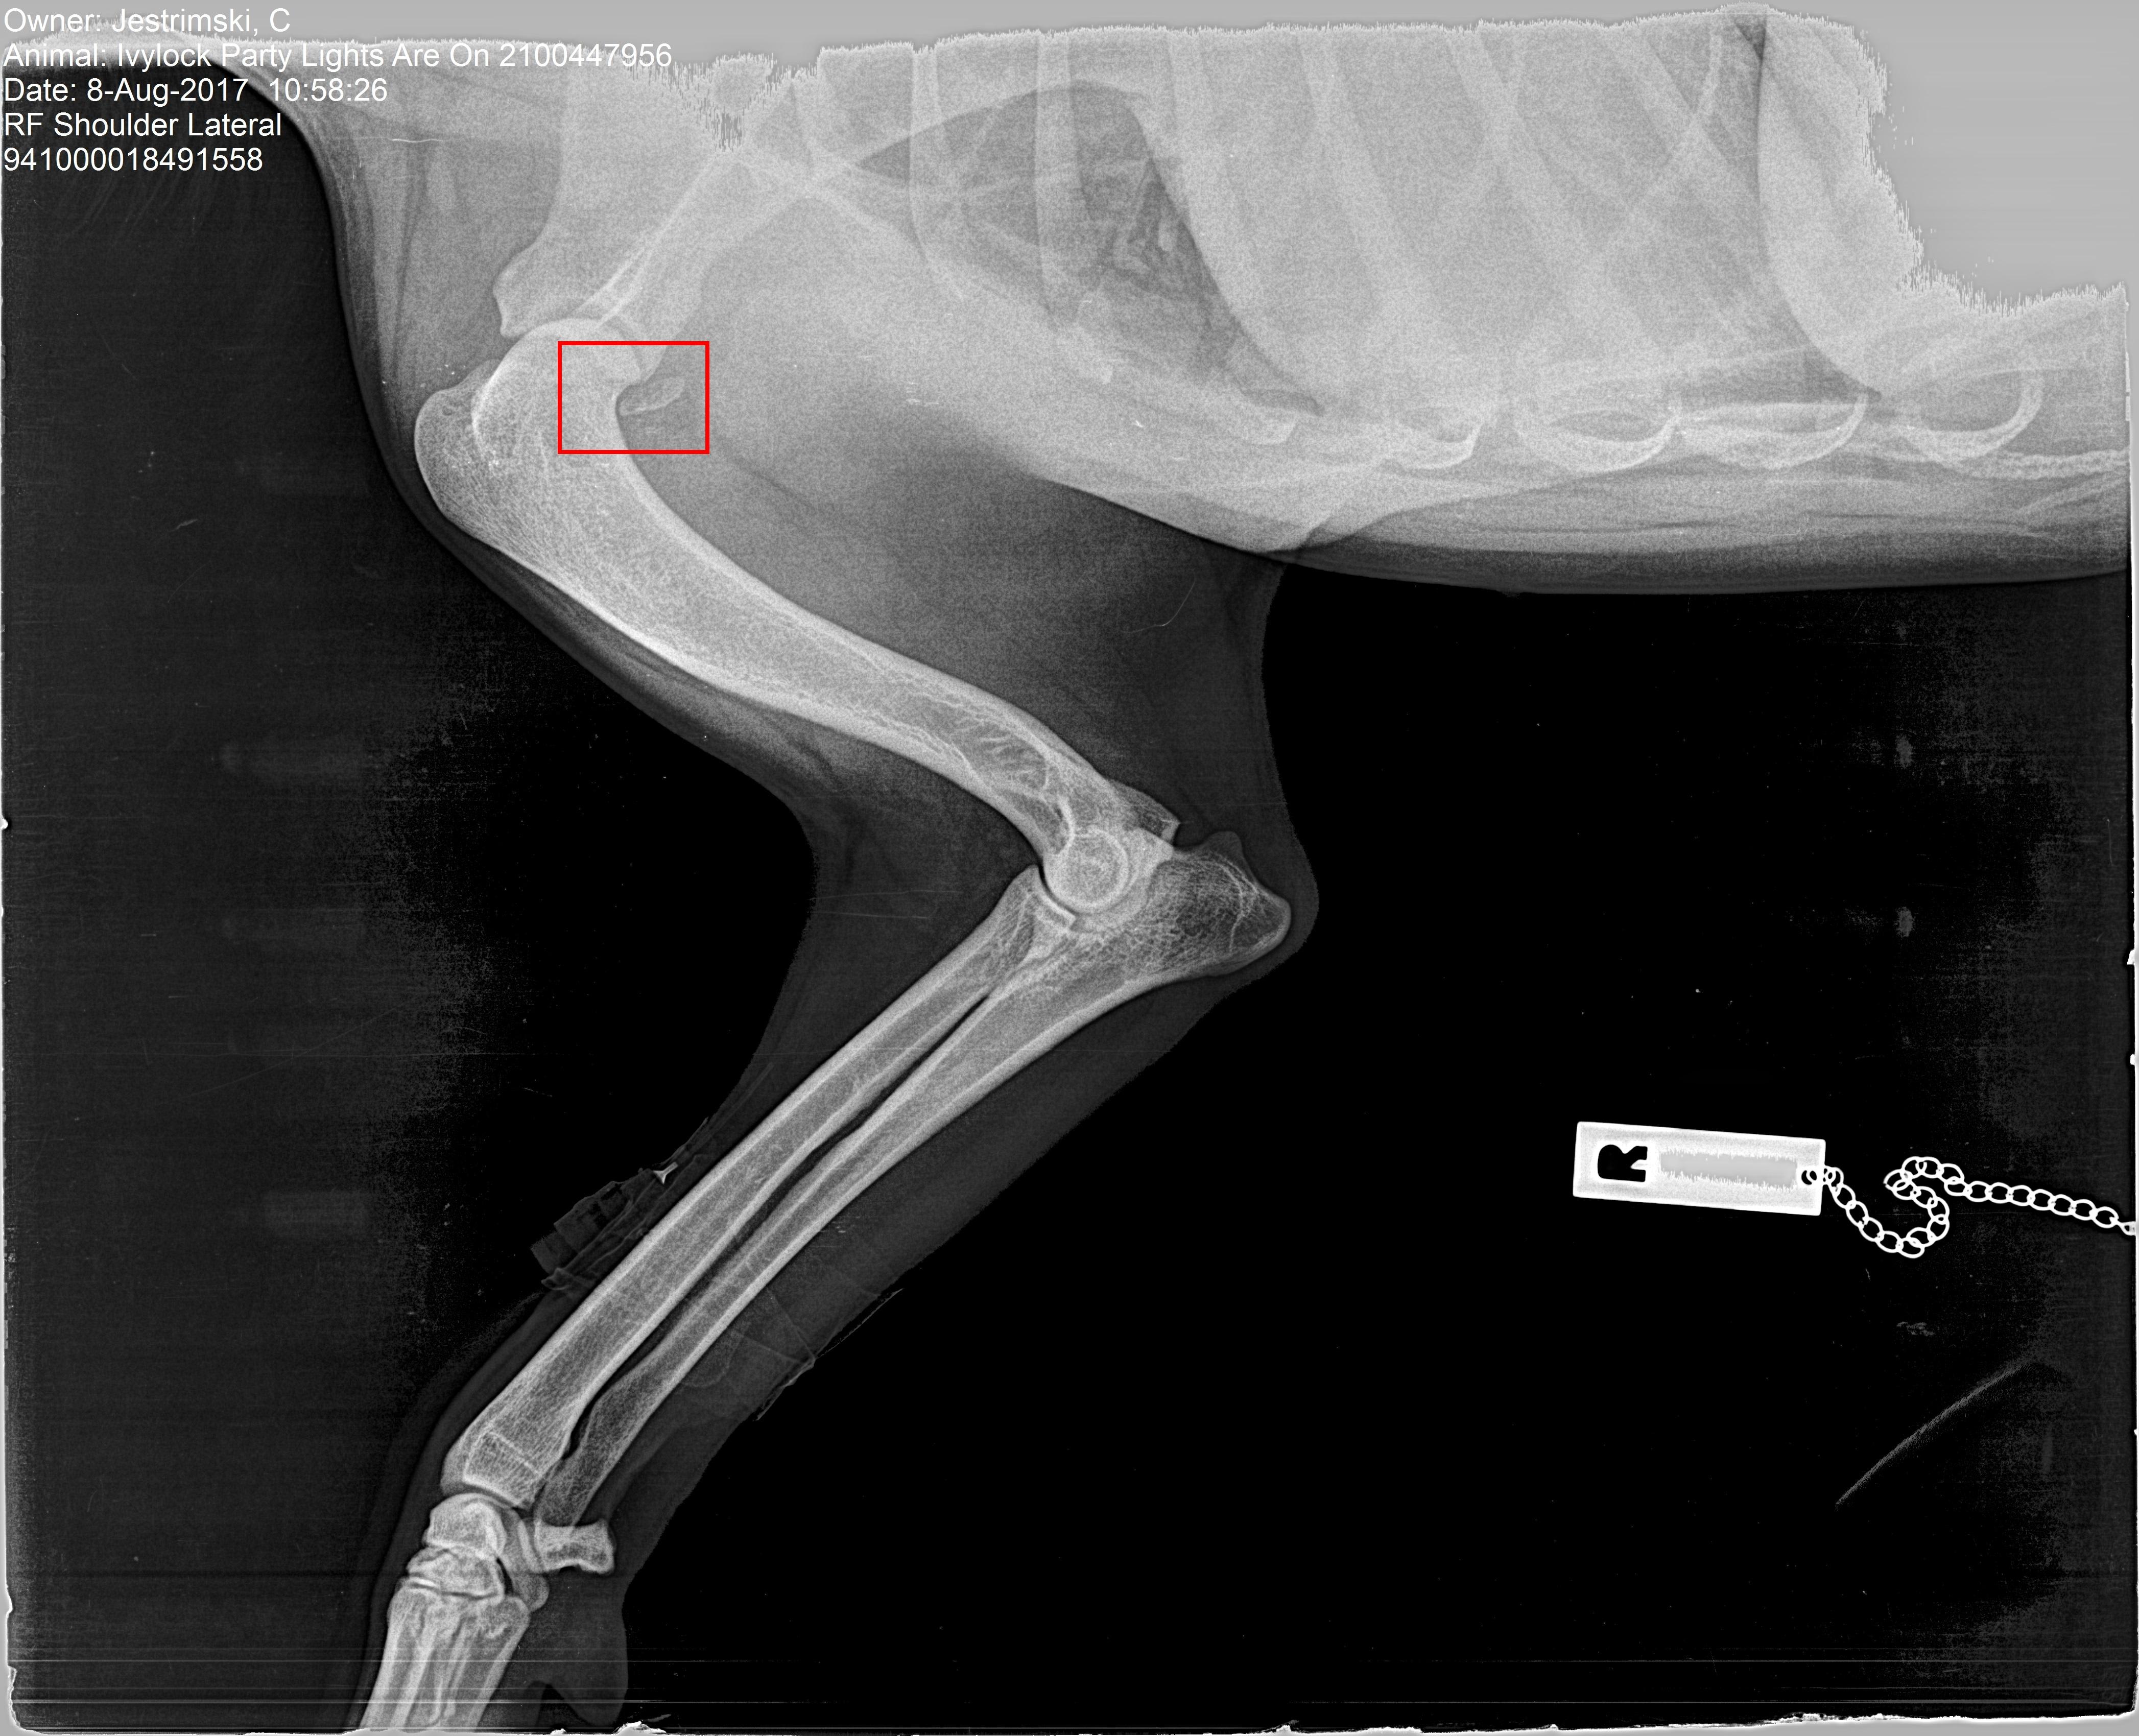

OCD I have an 18 mth Golden Retriever. At 6 mths she had a limp in the Right Shoulder after a collision with a larger dog. An x ray showed a small flap that the vet suggested would need an operation, if after weeks of rest and a change in diet the limp didn't disappear. The limp went away. We now xrayed her Hips & Elbows for breeding purposes, he checked the shoulder and can see a piece of cartilage detached from the joint. Should we operate even though there is no lameness or symptoms?

It may be a good idea to remove the chip, or at least go in arthroscopically (with a tiny camera) to see what the joint looks like and clean it up if necessary. My guess is there was significant trauma if it was enough to dislodge a chip there so it may predispose her to arthritis as she gets older, so going in while she's young and not having any signs could be beneficial. I would see if your veterinarian can recommend a boarded surgeon that performs arthroscopy to take a look at her and her x-rays and see what they think.